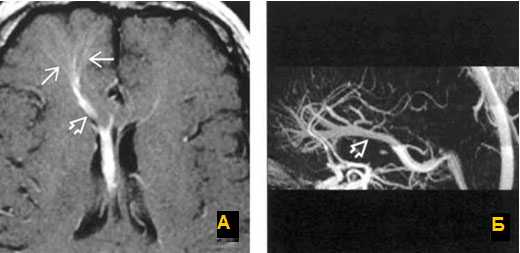

Исключали клинически значимую кардиологическую и лёгочную патологию. Обработку полученных данных проводили при помощи пакета статистических программ SPSS 10 с использованием критериев Стьюдента и Манна - Уитни. Результаты и их обсуждение. Учёт венозной фазы кровотока при МРТ-реконструкции сосудов головного мозга позволил верифицировать варианты развития поперечного и сигмовидного венозных синусов в виде их гипоплазии (рис.1) и полной аплазии (рис. 2).

Рис. 1. МРТ-визуализация сосудов головного мозга с венозной фазой мозгового кровотока. Гипоплазия левого сигмовидного и поперечного венозных синусов головного мозга. Существенное снижение кровотока в левых сигмовидном и поперечном синусах. Асимметрия кровотока в яремных венах - 86 и 14 %

Рис. 2. МРТ-визуализация сосудов головного мозга с венозной фазой мозгового кровотока. Отсутствует кровоток в левых сигмовидном и поперечном синусах. Асимметрия кровотока в яремных венах - 98 и 2 % (аплазия синусов)